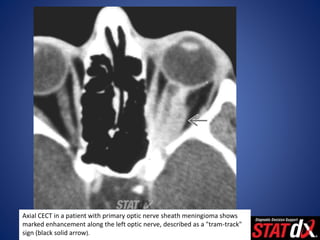

Axial CECT in a patient with primary optic nerve sheath meningioma shows

marked enhancement along the left optic nerve, described as a "tram-track"

sign (black solid arrow).

Axial CECT ina patient with primary optic nerve sheath meningioma shows marked enhancement along the left optic nerve, described as a "tram-track" sign (black solid arrow).